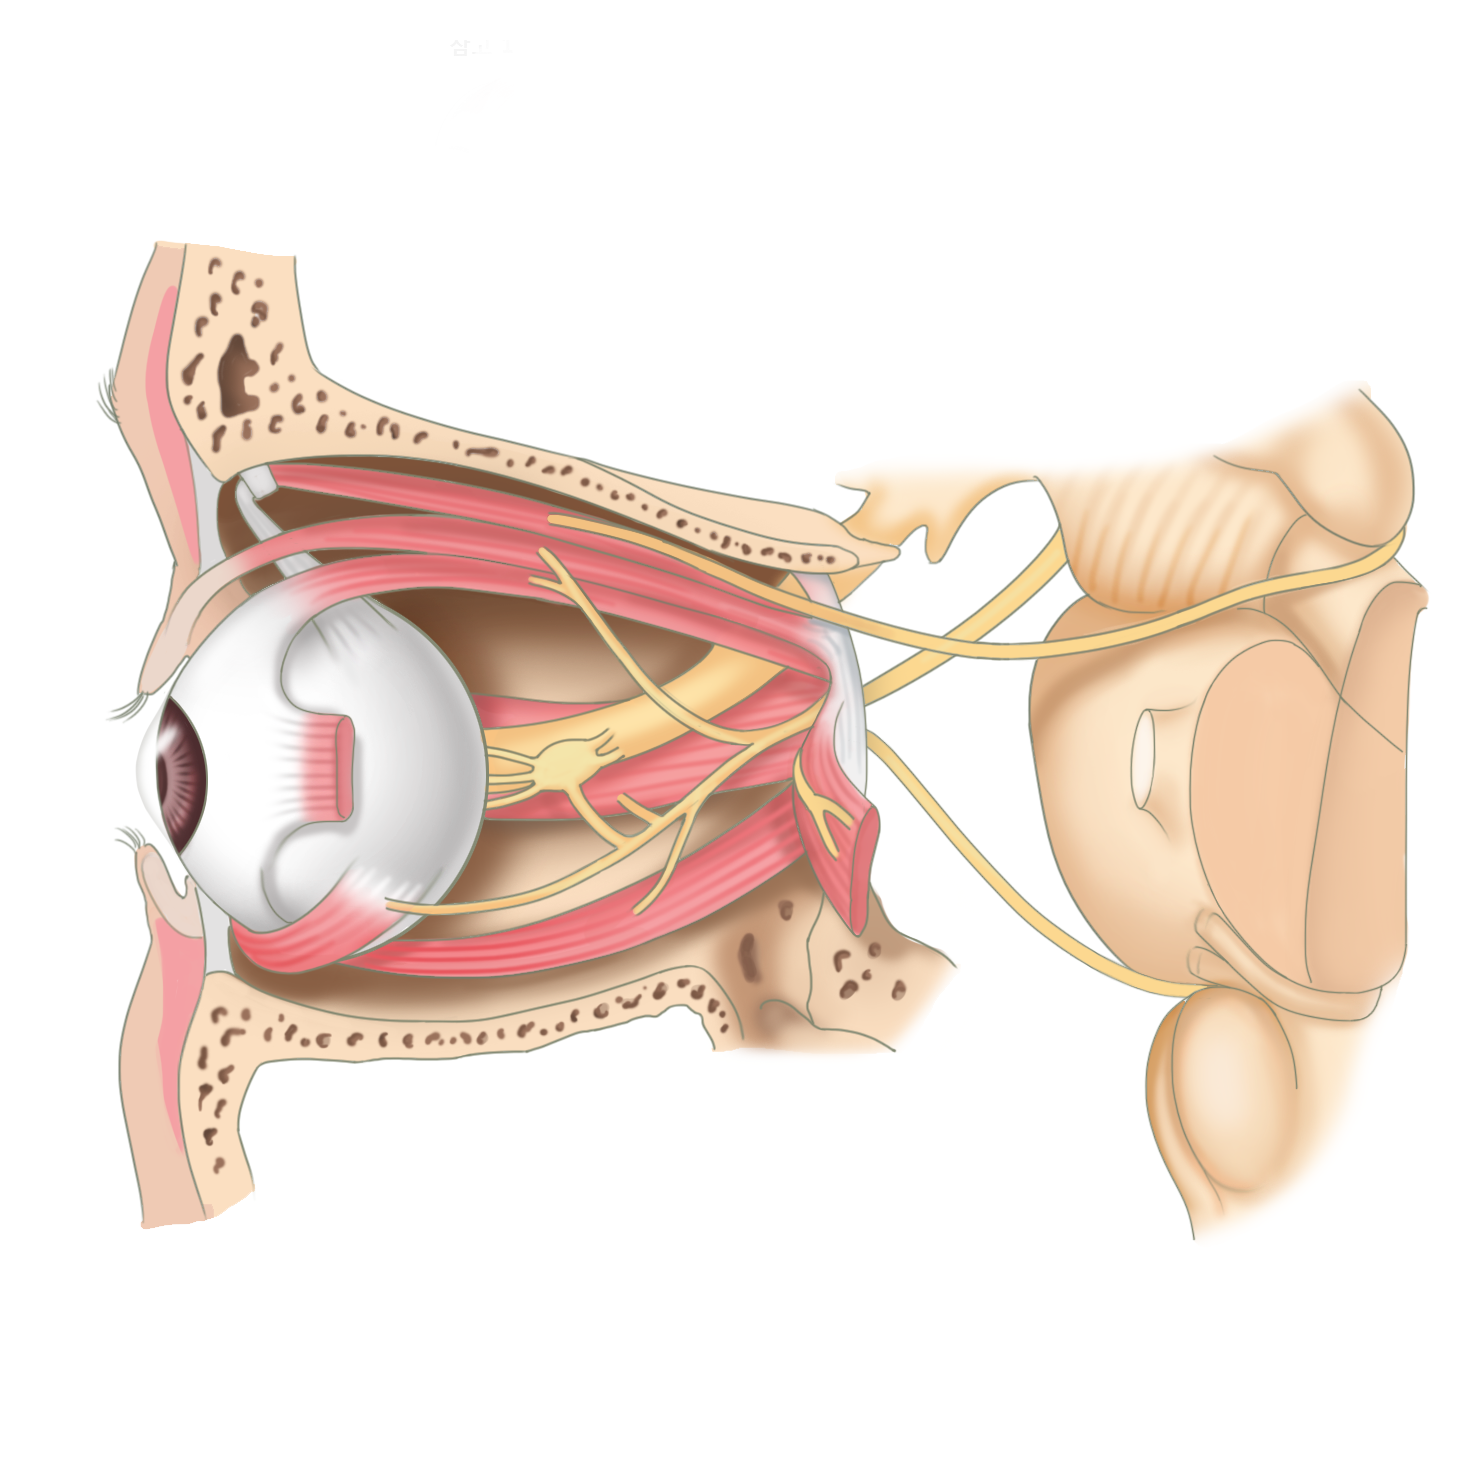

눈은 여러 단계의 구조를 통해 시각정보를 뇌에 전달하는 시각기관입니다.

얼굴의 윗쪽에 좌, 우로 위치하고 있습니다.

눈의 길이는 24mm 정도이며 탁구공만한 크기입니다. 눈의 구조는 역할에 따라 공막과 포도막, 망막으로 나눌 수 있습니다.

우리 눈의 눈꺼풀은 외부자극으로부터 눈을 보호하고 빛의 양을 조절하는 역할을 합니다. 눈물샘은 각막의 표면을 유지하고, 이물질을 세척해주는데 필요한 눈물을 배출합니다.